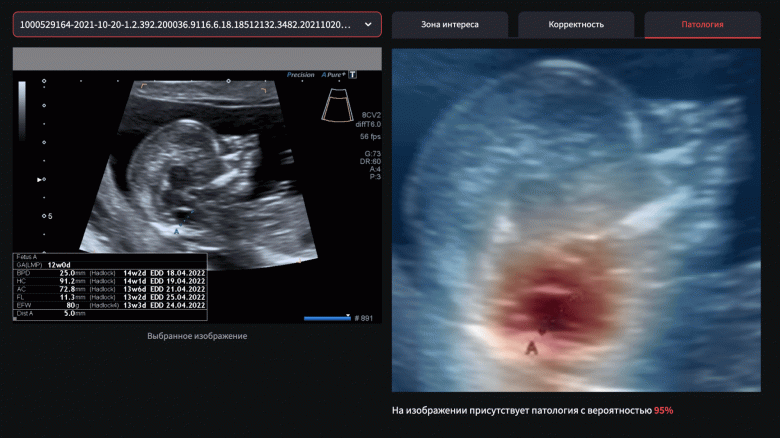

Команда Яндекса разработала нейросеть, которая поможет врачам обнаружить при УЗИ-исследовании беременных женщин симптомы spina bifida — тяжелого врожденного заболевания центральной нервной системы у детей. Об этом рассказала пресс-служба Яндекса.

Медицинский специалист может загрузить результаты УЗИ, сделанные во время первого скрининга. Решение автоматически проанализирует снимок и поможет врачу определить вероятность, с которой на изображении присутствуют признаки spina bifida. Если есть вероятность наличия патологии, врач сможет направить пациентку на дополнительное обследование в крупные перинатальные центры России, чтобы назначить дальнейшее лечение.